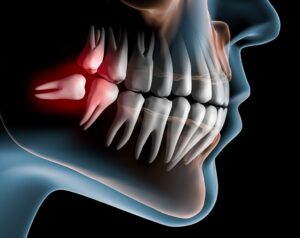

- Procedimentos como implantes, próteses sobre dente e sobre implante, pinos de fibra de vidro, coroas, facetas e lentes em porcelana, canal, extrações podem ser necessários em uma reabilitação.